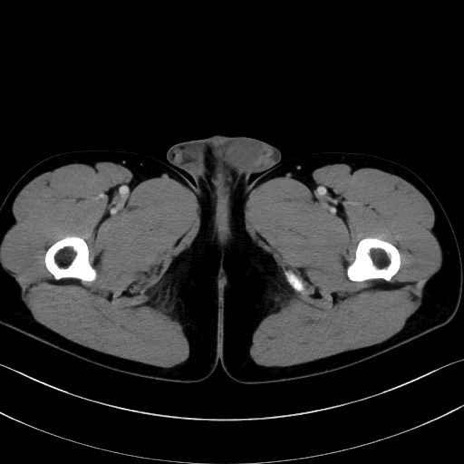

外閉鎖筋 (Obturator externus)